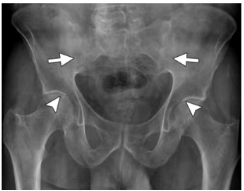

X线:对骶髂关节病变有诊断和分级意义,但只能检测慢性骨变化,这种变化通常需要几年时间才能变得明显,会导致诊断延迟。典型的骶髂关节炎可表现为关节面模糊、软骨下骨密度增高、骨质侵蚀、囊性变,随病情进展,可出现关节间隙狭窄甚至融合。